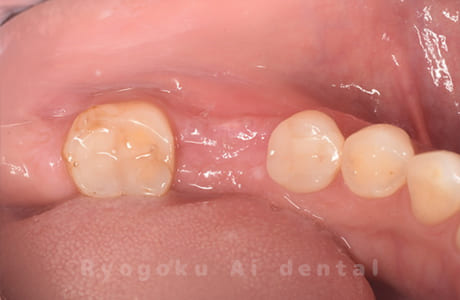

Case12

-

- 原因

- 左下7番歯牙破折

- 治療内容

- インプラント治療

- 治療費用

- 約600,000円

左下の奥歯が痛いとのことでご来院された患者様です。歯が完全に割れており、保存が不可能であったため、抜歯を行い、その際に骨に変わるお薬を入れ、十分な治癒を待ってからインプラント治療を行いました。経過良好で、大変満足されました。

<リスク・副作用>

治療後、痛みや違和感、出血、腫れなどが出る事があります。喫煙者、糖尿病などの方の場合、歯が生着しない場合があります。